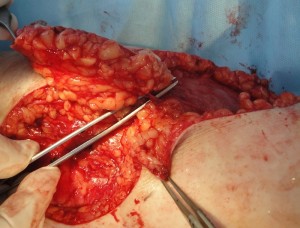

Проведено широкое иссечение новообразования в пределах неизмененных тканей радиоволновым методом Surgitron, гемостаз. В область дна раневого дефекта, размерами 10 х 9 см. предлежит большеберцовая кость, что является показанием к закрытию раны васкуляризированным лоскутом (Рис. 8А). После дессекции и выделения намеченный лоскут поднят, проведена визуализация перфорантов формирующих питающую ножку PPPF (Рис 8Б). Сам лоскут ротирован аксиллярно на 180 град. (Рис 8В), где адаптирован к краям раневого дефекта и фиксирован узловыми швами.1 Рана в реципиентной зоне сопоставлена с кожными краями лоскута и ушита, дефект донорской зоны закрыт путем сближения краев и наложением линейного шва. При этом важным моментом является соблюдение основного принципа пластической хирургии – ушивание раны без натяжения кожи. Послеоперационное течение гладкое. После заживления ран и верификации диагноза в гистологической лаборатории пациентка выписана к труду на 27 сутки после операции. После удаления обширного новообразования на голени путем пластики PPPF сформирован устойчивый кожный покров, максимально близкий по структуре и цвету утраченному вследствие заболевания, без значительного нарушения контуров конечности как в донорской, так и в реципиентной зоне. Пациентка полностью удовлетворена результатом лечения (Рис 8Г).

Рис. 8. А – цифровое фото раневого дефекта на голени после иссечения новообразования.

Б – вид поднятого после дессекции лоскута, визуализация перфорантов, формирующих питающую ножку. В – вид лоскута после аксилярной ротации и адаптации в реципиентную зону раневого дефекта. Г – цифровое фото голени в раннем послеоперационном периоде, после снятия швов и перед выпиской из клиники. Отмечается адекватное восстановление кожного покрова без нарушения контуров конечности, как в донорской, так и в реципиентной зоне. Д – отдаленный результат, через 20 месяцев после операции; рецидива заболевания нет, пациент полностью удовлетворен состоянием кожного покрова, контуром голени и функцией нижней конечности.